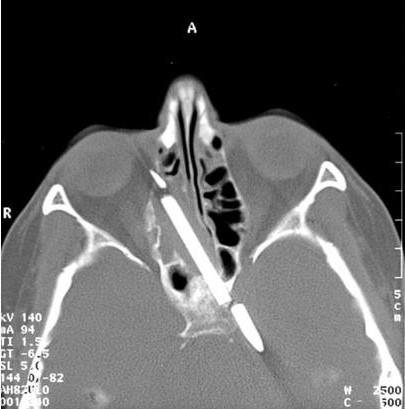

2. 30-летняя больная булимией жительница г. Атланта случайно

проглотила столовый нож, демонстрируя своим друзьям отсутствие у

себя рвотного рефлекса.